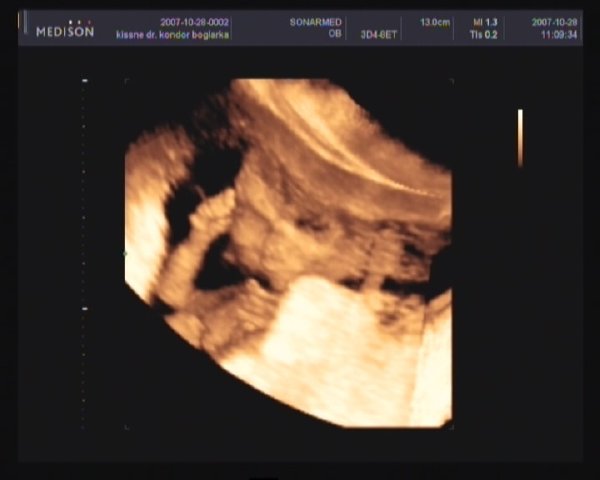

Bejutottam a 10 perces ingyenes UH-ra.

Itt mar tutira latszott, hogy kislany!